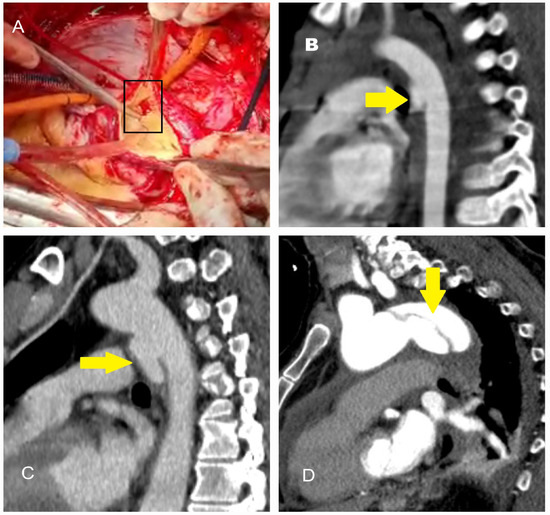

5.2.3. Computed Tomography